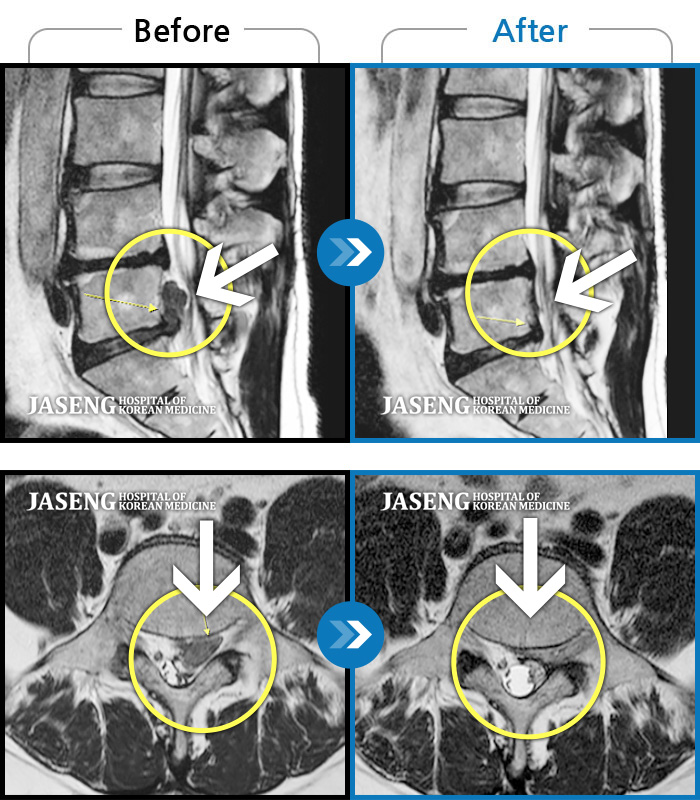

• 허리디스크